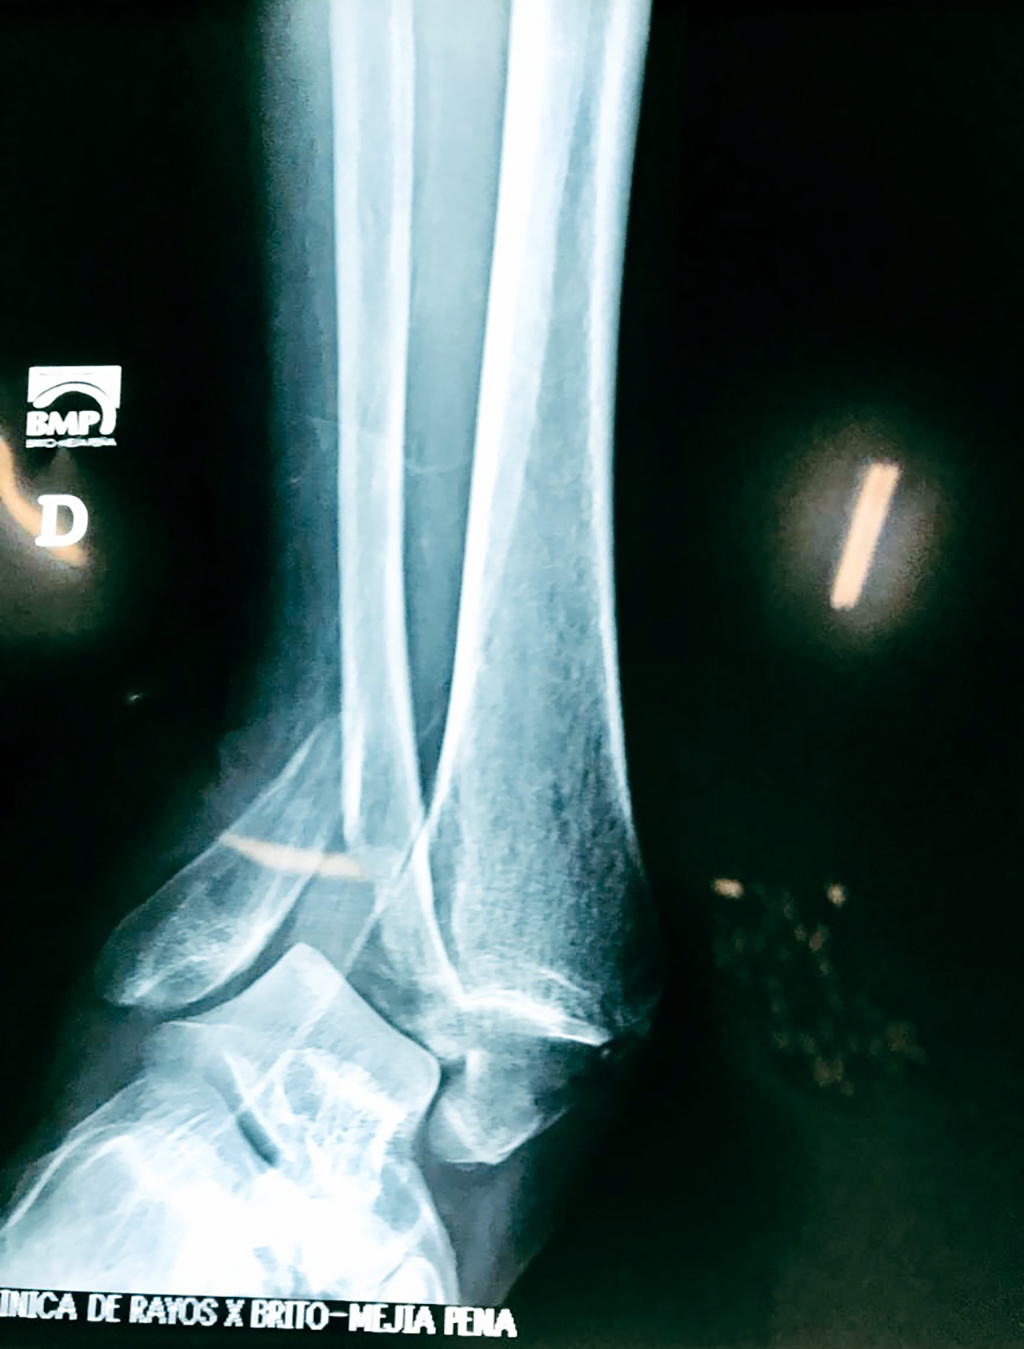

Una fractura de tobillo es la rotura de uno o más de los huesos del tobillo. Estas fracturas pueden ser:

• Parciales (el hueso está sólo parcialmente fisurado, no del todo).

• Completas (el hueso está perforado y está en 2 partes).

• Producirse en uno o ambos lados del tobillo.

Cuando se necesita cirugía, es probable que esta implique el uso de clavijas de metal, tornillos o placas para sostener los huesos en su lugar mientras la fractura se consolida. Los elementos de soporte pueden ser temporales o permanentes.

Tobillo

Detail Download